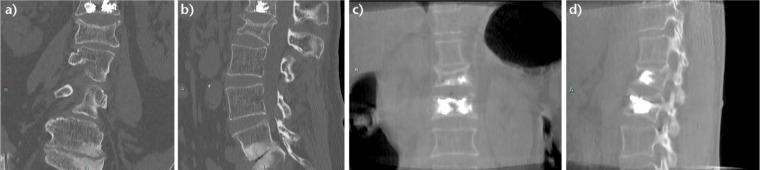

Thoracolumbar vertebral fracture incidents usually occur secondary to a high velocity trauma in young patients and to minor trauma or spontaneously in older people.Osteoporotic vertebral fractures are the most common osteoporotic fractures and affect one-fifth of the osteoporotic population.Percutaneous fixation by 'vertebroplasty' is a tempting alternative for open surgical management of these fractures.Despite discouraging initial results of early trials for vertebroplasty, cement augmentation proved its superiority for the treatment of symptomatic osteoporotic vertebral fracture when compared with optimal medical treatment.Early intervention is also gaining ground recently.Kyphoplasty has the advantage over vertebroplasty of reducing kyphosis and cement leak.Stentoplasty, a new variant of cement augmentation, is also showing promising outcomes.In this review, we describe the additional techniques of cement augmentation, stressing the important aspects for success, and recommend a thorough evaluation of thoracolumbar fractures in osteoporotic patients to select eligible patients that will benefit the most from percutaneous augmentation. A detailed treatment algorithm is then proposed. Cite this article: EFORT Open Rev 2017;2:293-299. DOI: 10.1302/2058-5241.2.160057.

胸腰椎骨折事件通常继发于年轻患者的高速创伤以及老年人的轻微创伤或自发发生。骨质疏松性椎体骨折是最常见的骨质疏松性骨折,影响五分之一的骨质疏松人群。“椎体成形术”经皮固定是这些骨折开放手术治疗的一种诱人替代方法。尽管椎体成形术早期试验的初步结果令人沮丧,但与最佳药物治疗相比,骨水泥强化已证明其在治疗有症状的骨质疏松性椎体骨折方面具有优越性。早期干预最近也越来越受到重视。后凸成形术比椎体成形术具有减少后凸和骨水泥渗漏的优势。支架成形术是骨水泥强化的一种新变体,也显示出有希望的结果。在本综述中,我们描述了骨水泥强化的其他技术,强调成功的重要方面,并建议对骨质疏松患者的胸腰椎骨折进行全面评估,以选择最能从经皮强化中获益的合格患者。然后提出了详细的治疗算法。引用本文:EFORT Open Rev 2017;2:293 - 299。DOI: 10.1302/2058 - 5241.2.160057。